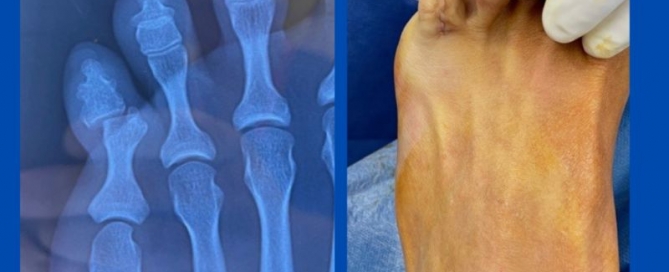

Subungual exostosis

Blog's main page I see a regular amount of subungual exostosis throughout the year. Typically they have been treated as ingrown toenails (IGTN) first. The GP and the podiatrist may [...]